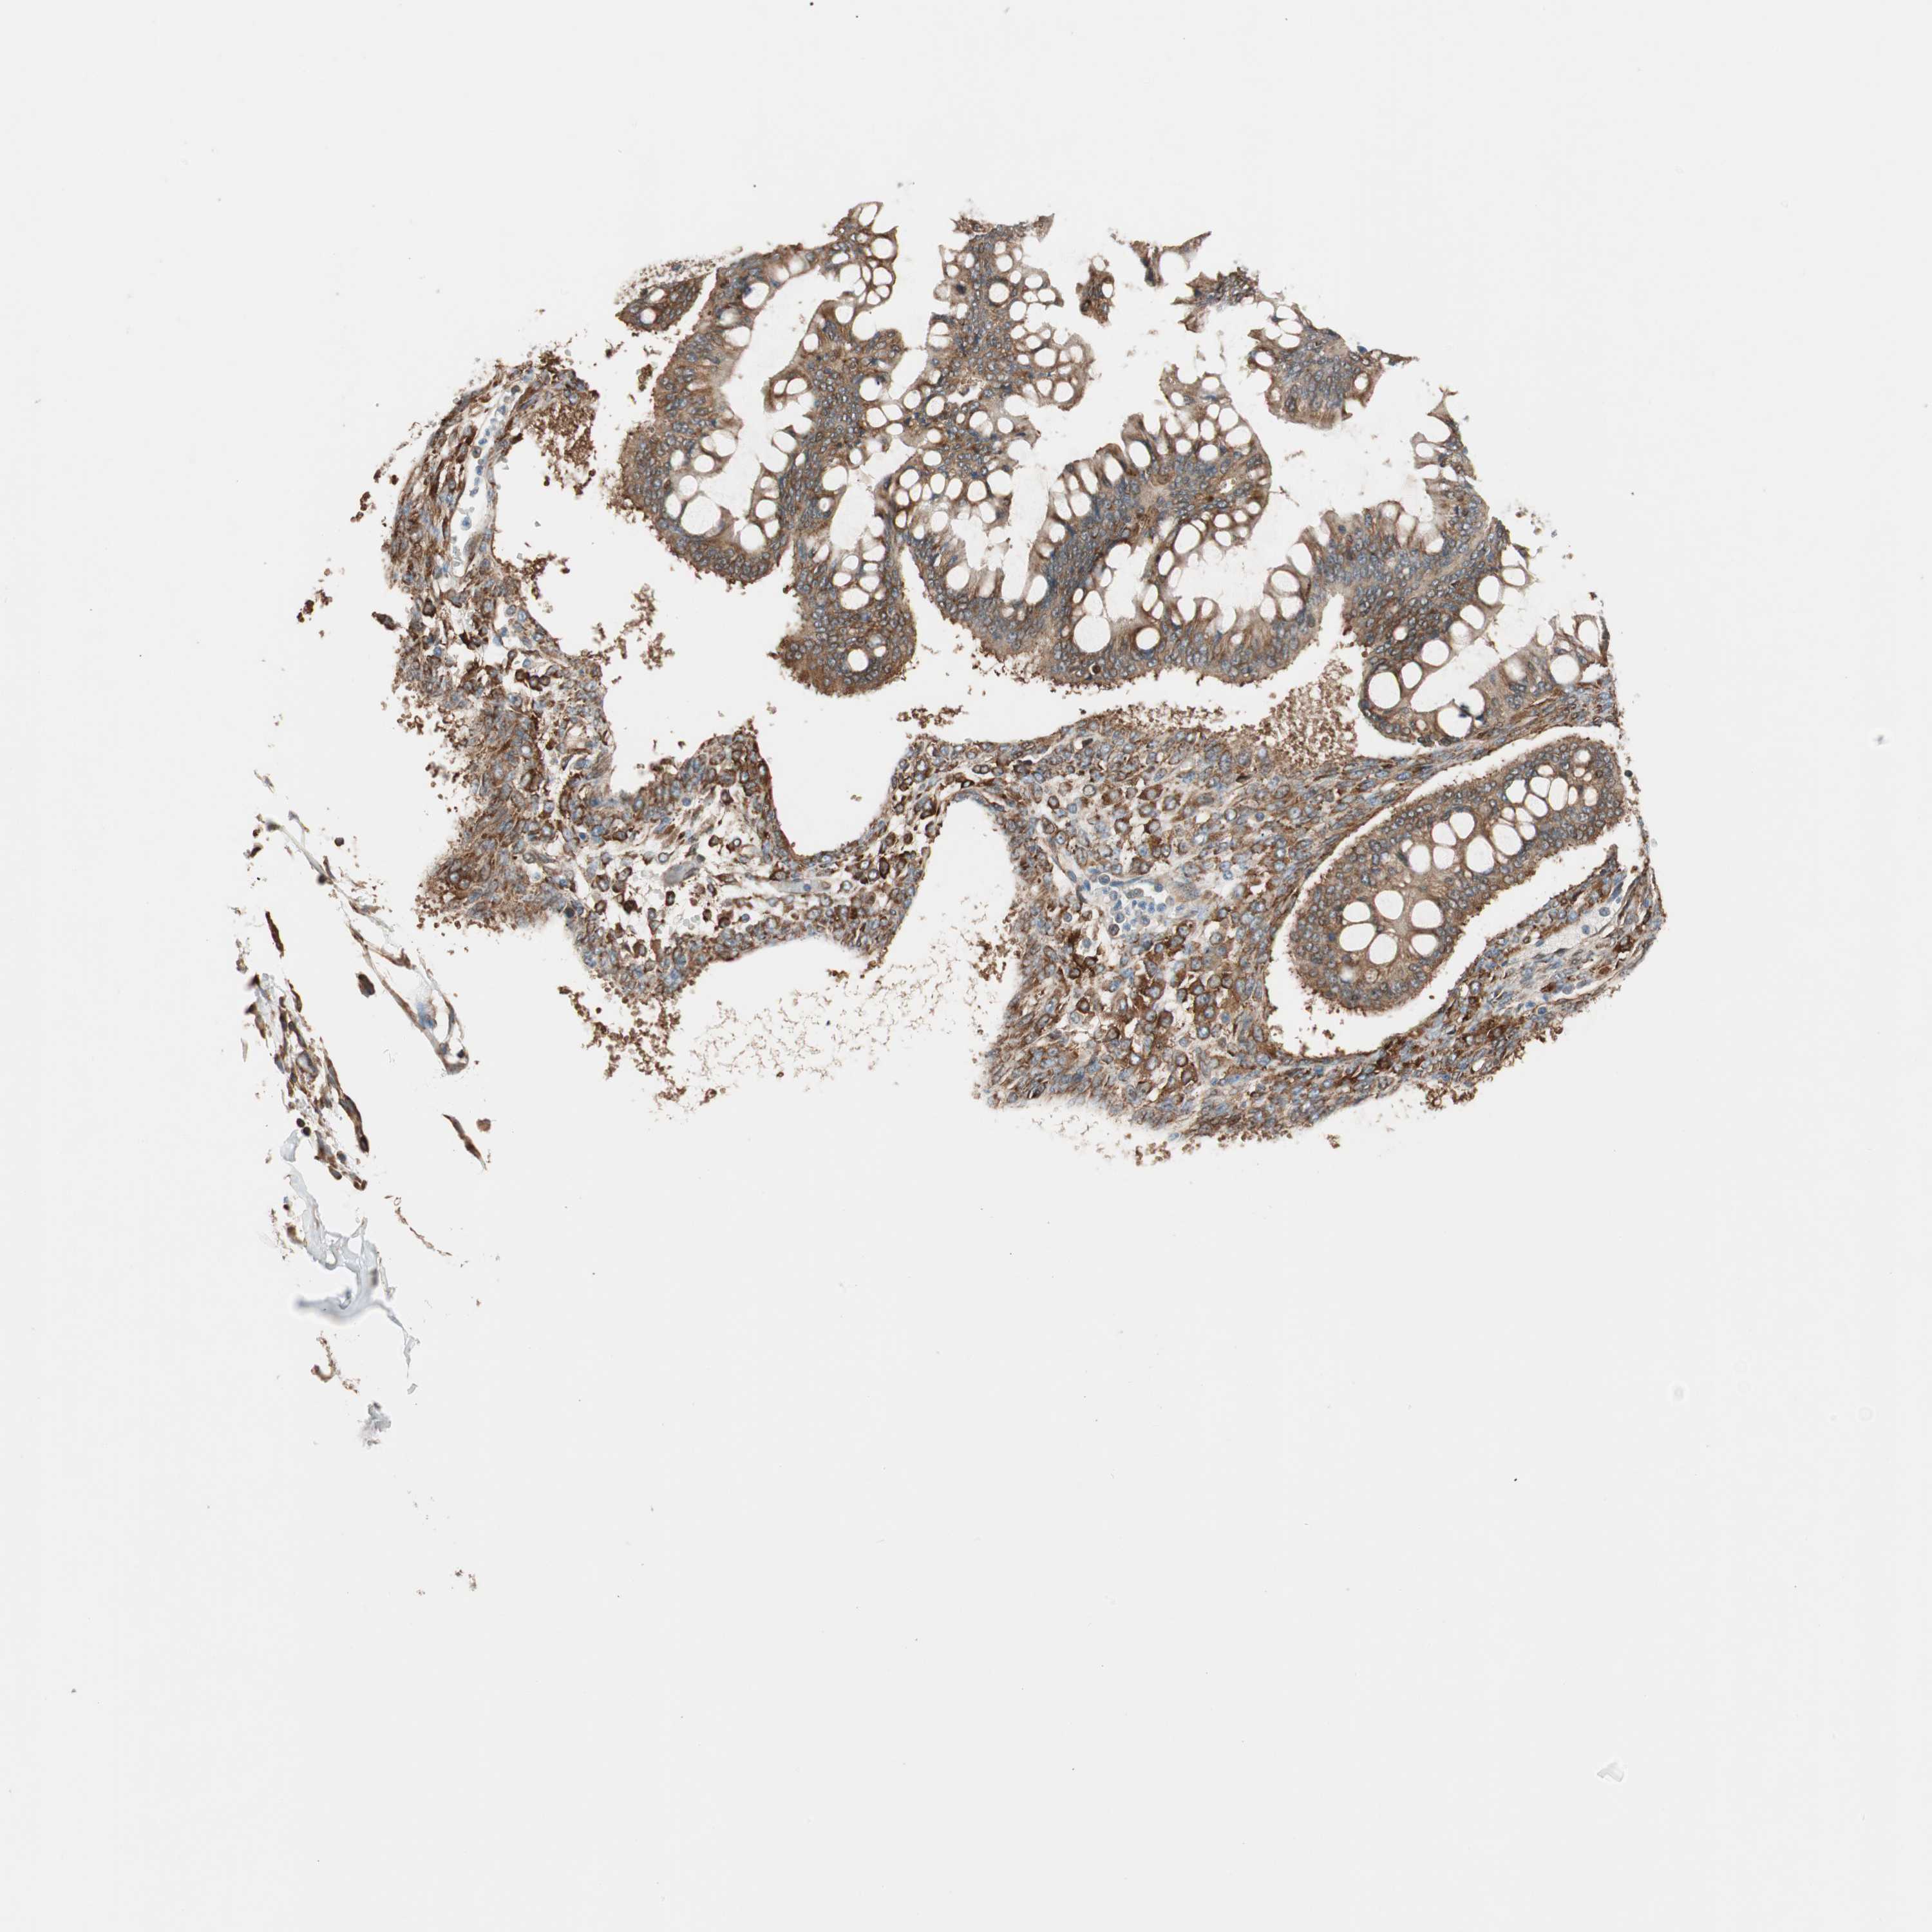

OVARIAN CANCER - Protein expressioni

A mouse-over function shows sample information and annotation data. Click on an image to view it in a full screen mode. Samples can be filtered based on level of antibody staining by selecting one or several of the following categories: high, medium, low and not detected. The assay and annotation is described here.

Note that samples used for immunohistochemistry by the Human Protein Atlas do not correspond to samples in the TCGA dataset.

Antibody stainingi

Antibody staining in the annotated cell types in the current human tissue is reported as not detected, low, medium, or high, based on conventional immunohistochemistry profiling in selected tissues. This score is based on the combination of the staining intensity and fraction of stained cells.

Each image is clickable and will lead to virtual microscopy that enables deeper exploration of all samples and also displays staining intensity scores, fraction scores and subcellular localization as well as patient and tissue information for each sample.

Antibody HPA005750

Antibody CAB005399

Carcinoma, NOS

Cystadenocarcinoma, serous, NOS